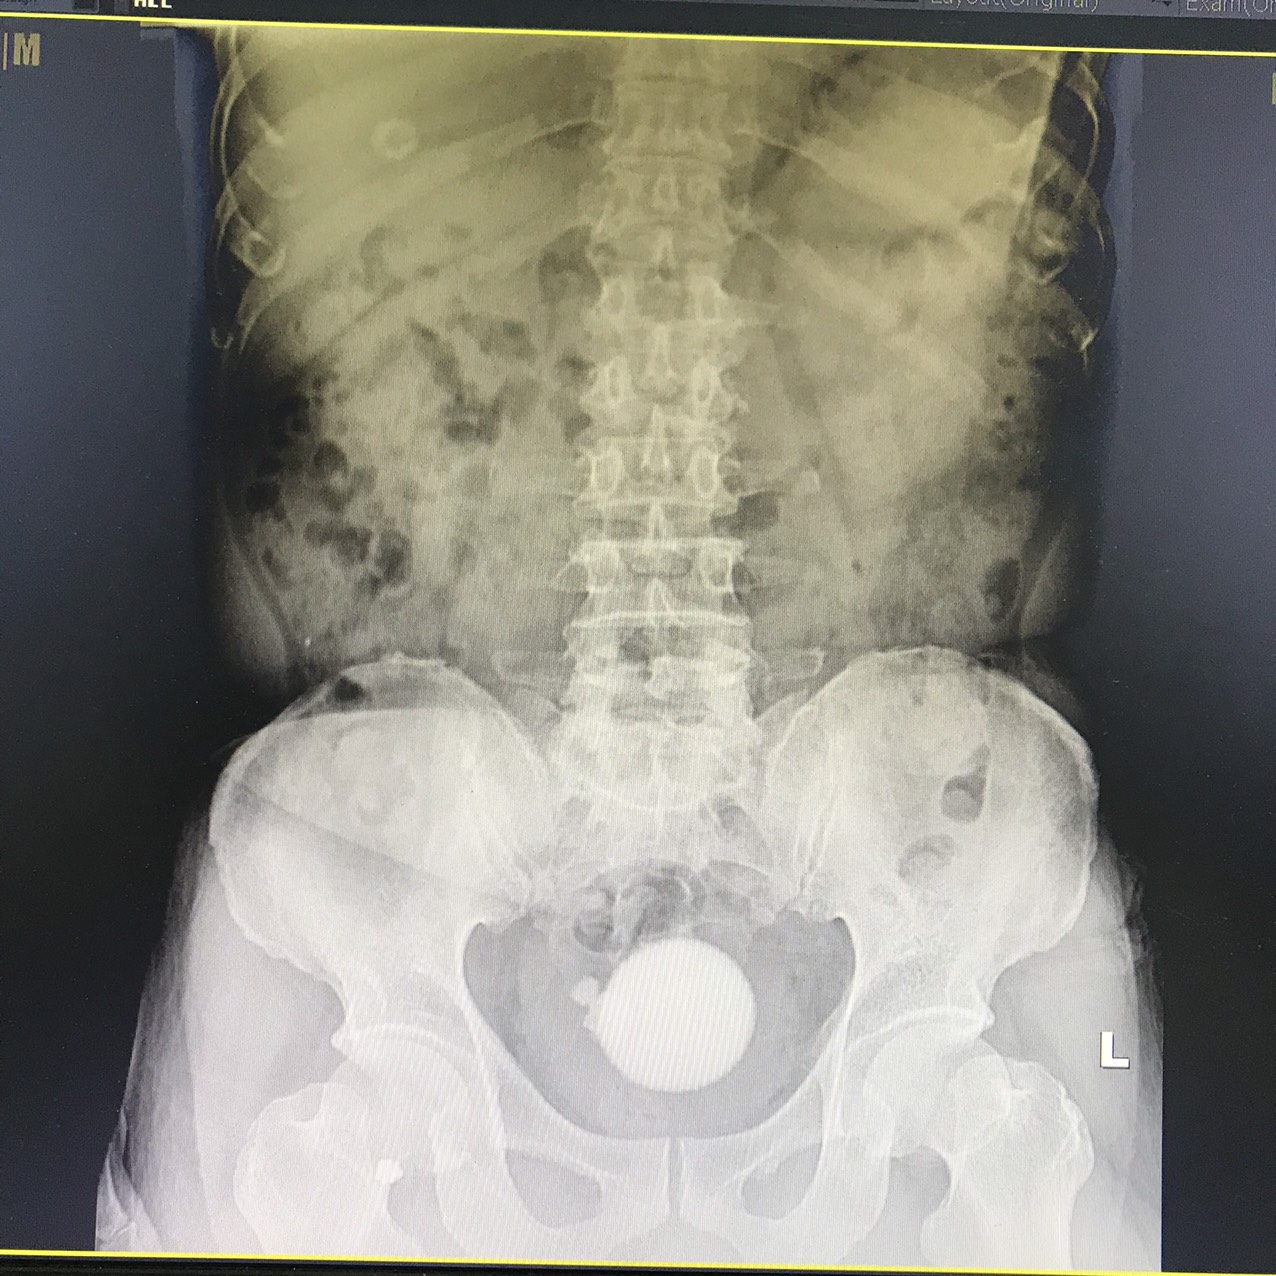

Bệnh nhân T.Q.C, 71 tuổi, ở Hồ Nam, Lê Chân, Hải Phòng xuất hiện đái khó nhiều ngày, đái buốt, rắt, đái tắc, tia tiểu yếu kèm theo có đau tức hạ vị, buốt niệu đạo. Qua thăm khám và thực hiện các cận lâm sàng cần thiết, các bác sĩ Bệnh viện đa khoa Quốc tế Hải Phòng chẩn đoán phát hiện người bệnh có đồng thời nhiều sỏi: sỏi bàng quang kích thước lớn (hơn 5cm), sỏi niệu quản phải 1/3 dưới, kích thước (hơn 1cm), nhiều sỏi trong nhiều túi thừa bàng quang.

Để chấm dứt tình trạng đái buốt, rắt, đau đớn, khó chịu kéo dài và các biến chứng nặng nề có thể xảy ra cho người bệnh, các bác sĩ Khoa Ngoại thận tiết niệu – Nam học đã quyết định tiến hành nội soi tán sỏi cho bệnh nhân. Người bệnh có 01 sỏi nằm choán chỗ toàn bộ bàng quang (kích thước thực tế khoảng 5 x 7 cm) và nhiều sỏi nằm trong túi thừa (03 viên sỏi nằm ở hai túi thừa, vị trí thành sau bên phải, cạnh lỗ niệu quản phải). Đặc điểm sỏi rắn chắc, gai góc và xù xì, khó tán; cổ túi thừa nhỏ niệu quản phù nề gây khó khăn trong quá trình thực hiện. Điều đặc biệt hơn, với kích thước sỏi bàng quang lớn, nếu mổ mở người bệnh sẽ phải chịu một vết mổ dài trên thành bụng và bàng quang để lấy sỏi gây đau đớn, tiềm ẩn nhiều nguy cơ như: chảy máu, nhiễm trùng vết mổ, kéo dài thời gian nằm viện, ảnh hưởng đến sức khỏe và kinh tế cho người bệnh.